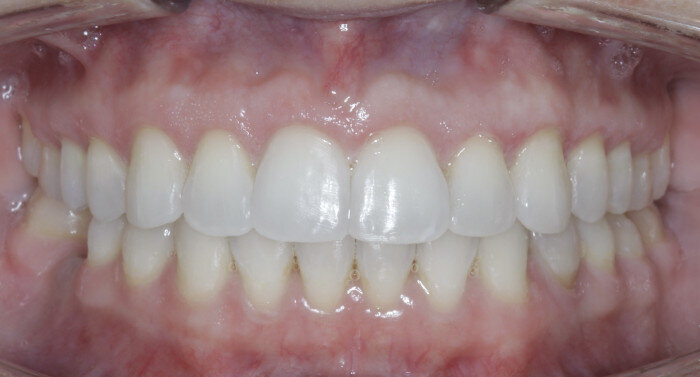

Once the intrusion has been completed, the TADs are tied to the wire and vertical elastics are used to close the bite without relapse of the intrusion. If buccal crown tip is seen, owing to the movement created by the intrusion, a power chain torquing sling is used to encourage lingual crown tipping and to prevent flaring of the incisors (Fig. 9). Once the case has been completed, the appliance is removed and a gingivectomy is performed to idealise the tissue shape and the final contours are made to the hard tissue (Figs. 10–12, end of treatment).

In some cases, intrusion may occur asymmetrically (one side faster than another, or the anterior faster than the posterior). For these occurrences, when one area has been completed with intrusion, the TAD is tied to the wire and intrusion continues in the others until all intrusion has been completed. A gingivectomy and hard-tissue contouring are completed (Figs. 27–29, end of treatment).